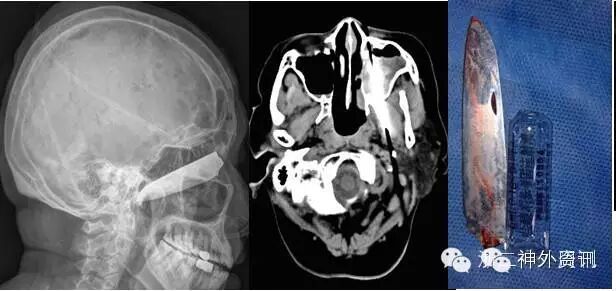

图8. 折叠刀刺入颅内,成功拔除(患者,男,37岁,A、B术前CT,C术后CT复查)。

图9. 钢棒入颅,成功拔除(患者,男,55岁,A、B术前CT,C术后CT复查)。

图10. 钢钩扎入眶颅,顺利拔除(患者,女,35岁,A、B、C术前,D术后CT复查,E取出钢钩)。

图11. 钢钎经口咽入颅,成功拔除(有点类似于本病例,患者,男,44岁)。

图12. 刀片插入眶颅,顺利拔除(患者,女,67岁)。

图13. 拔除枯竹(患者,女,61岁,详见浙二神外周刊(八))。